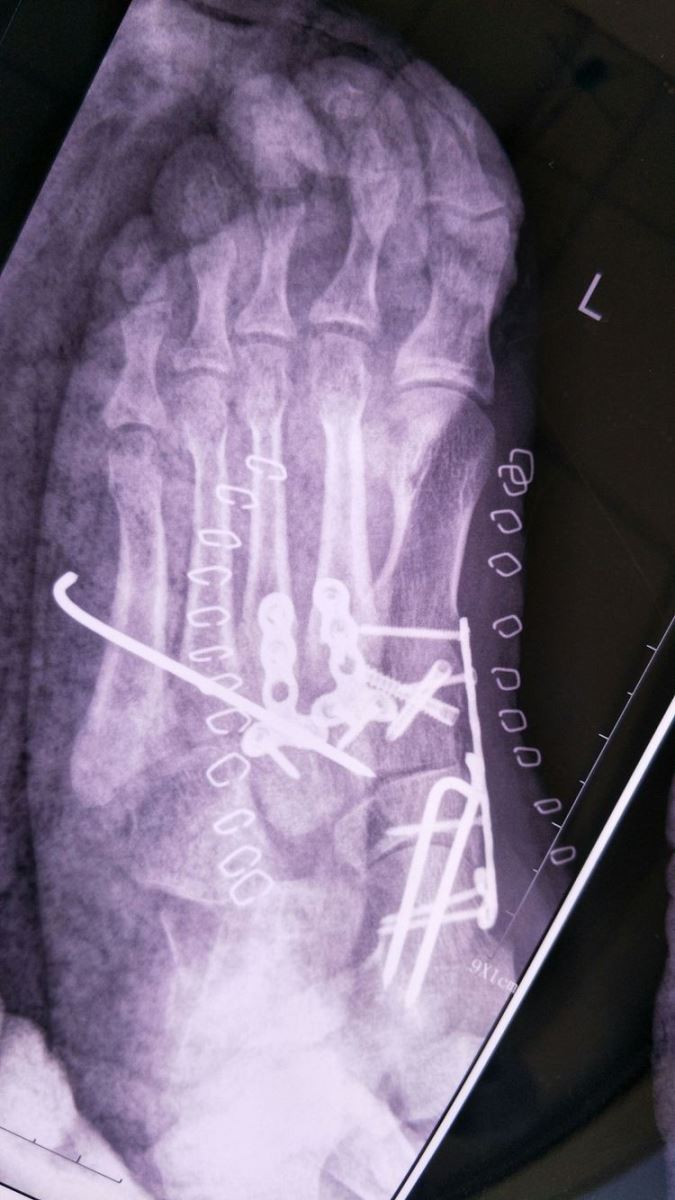

术后X光:Chaopart关节脱位纠正,固定良好,跖跗关节脱位纠正,固定良好。